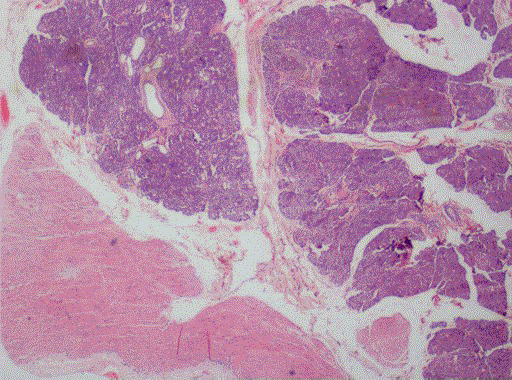

Figure 3. Photomicrograph shows sub epithelial pancreatic tissue (H&E x20).